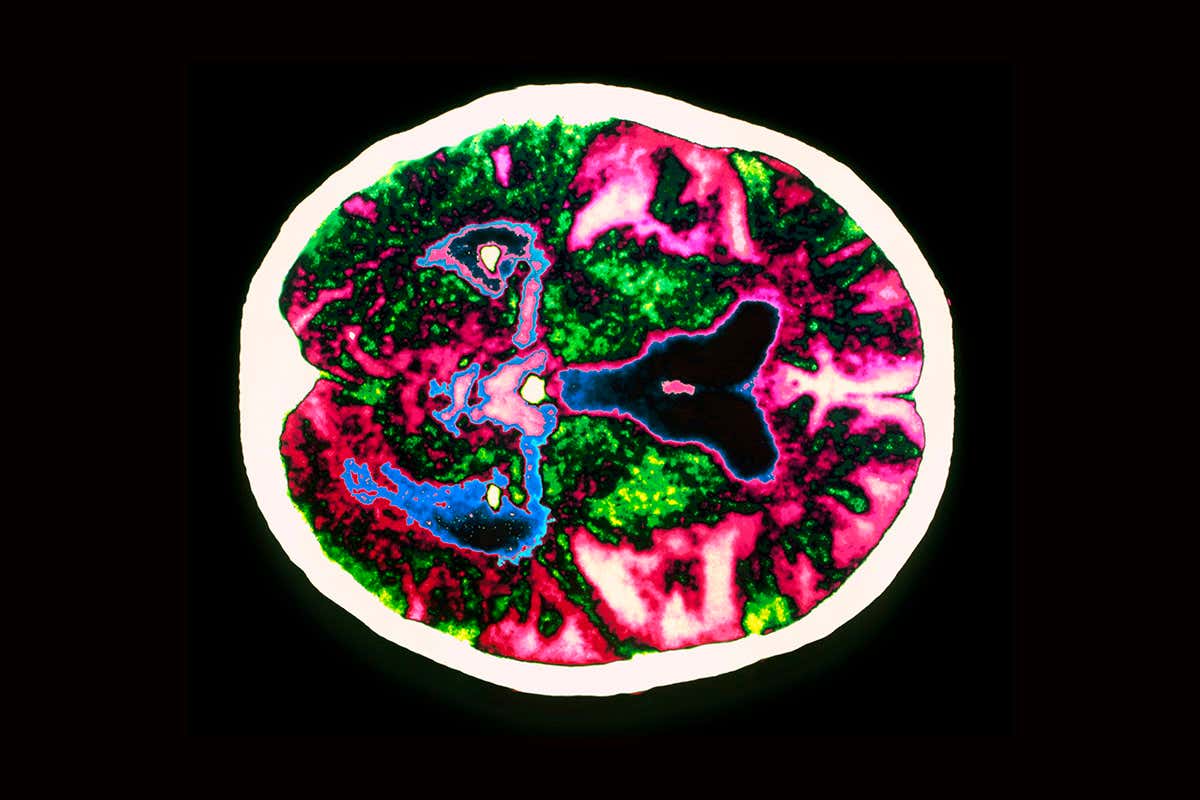

Alzheimer’s disease: is chronic inflammation to blame? Zephyr/Science Photo Library